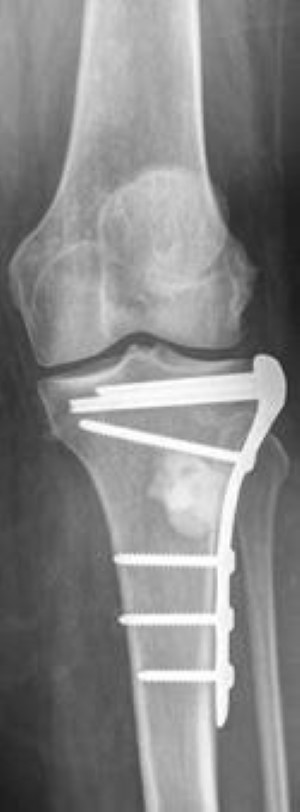

plate and screw fixation of distal femur for MBD

In this X-ray, the weakened lower end of the femur has been stabilized with a plate and screws. In this case, plate-and-screw fixation will maintain stability and allow the patient to bear weight on the leg.